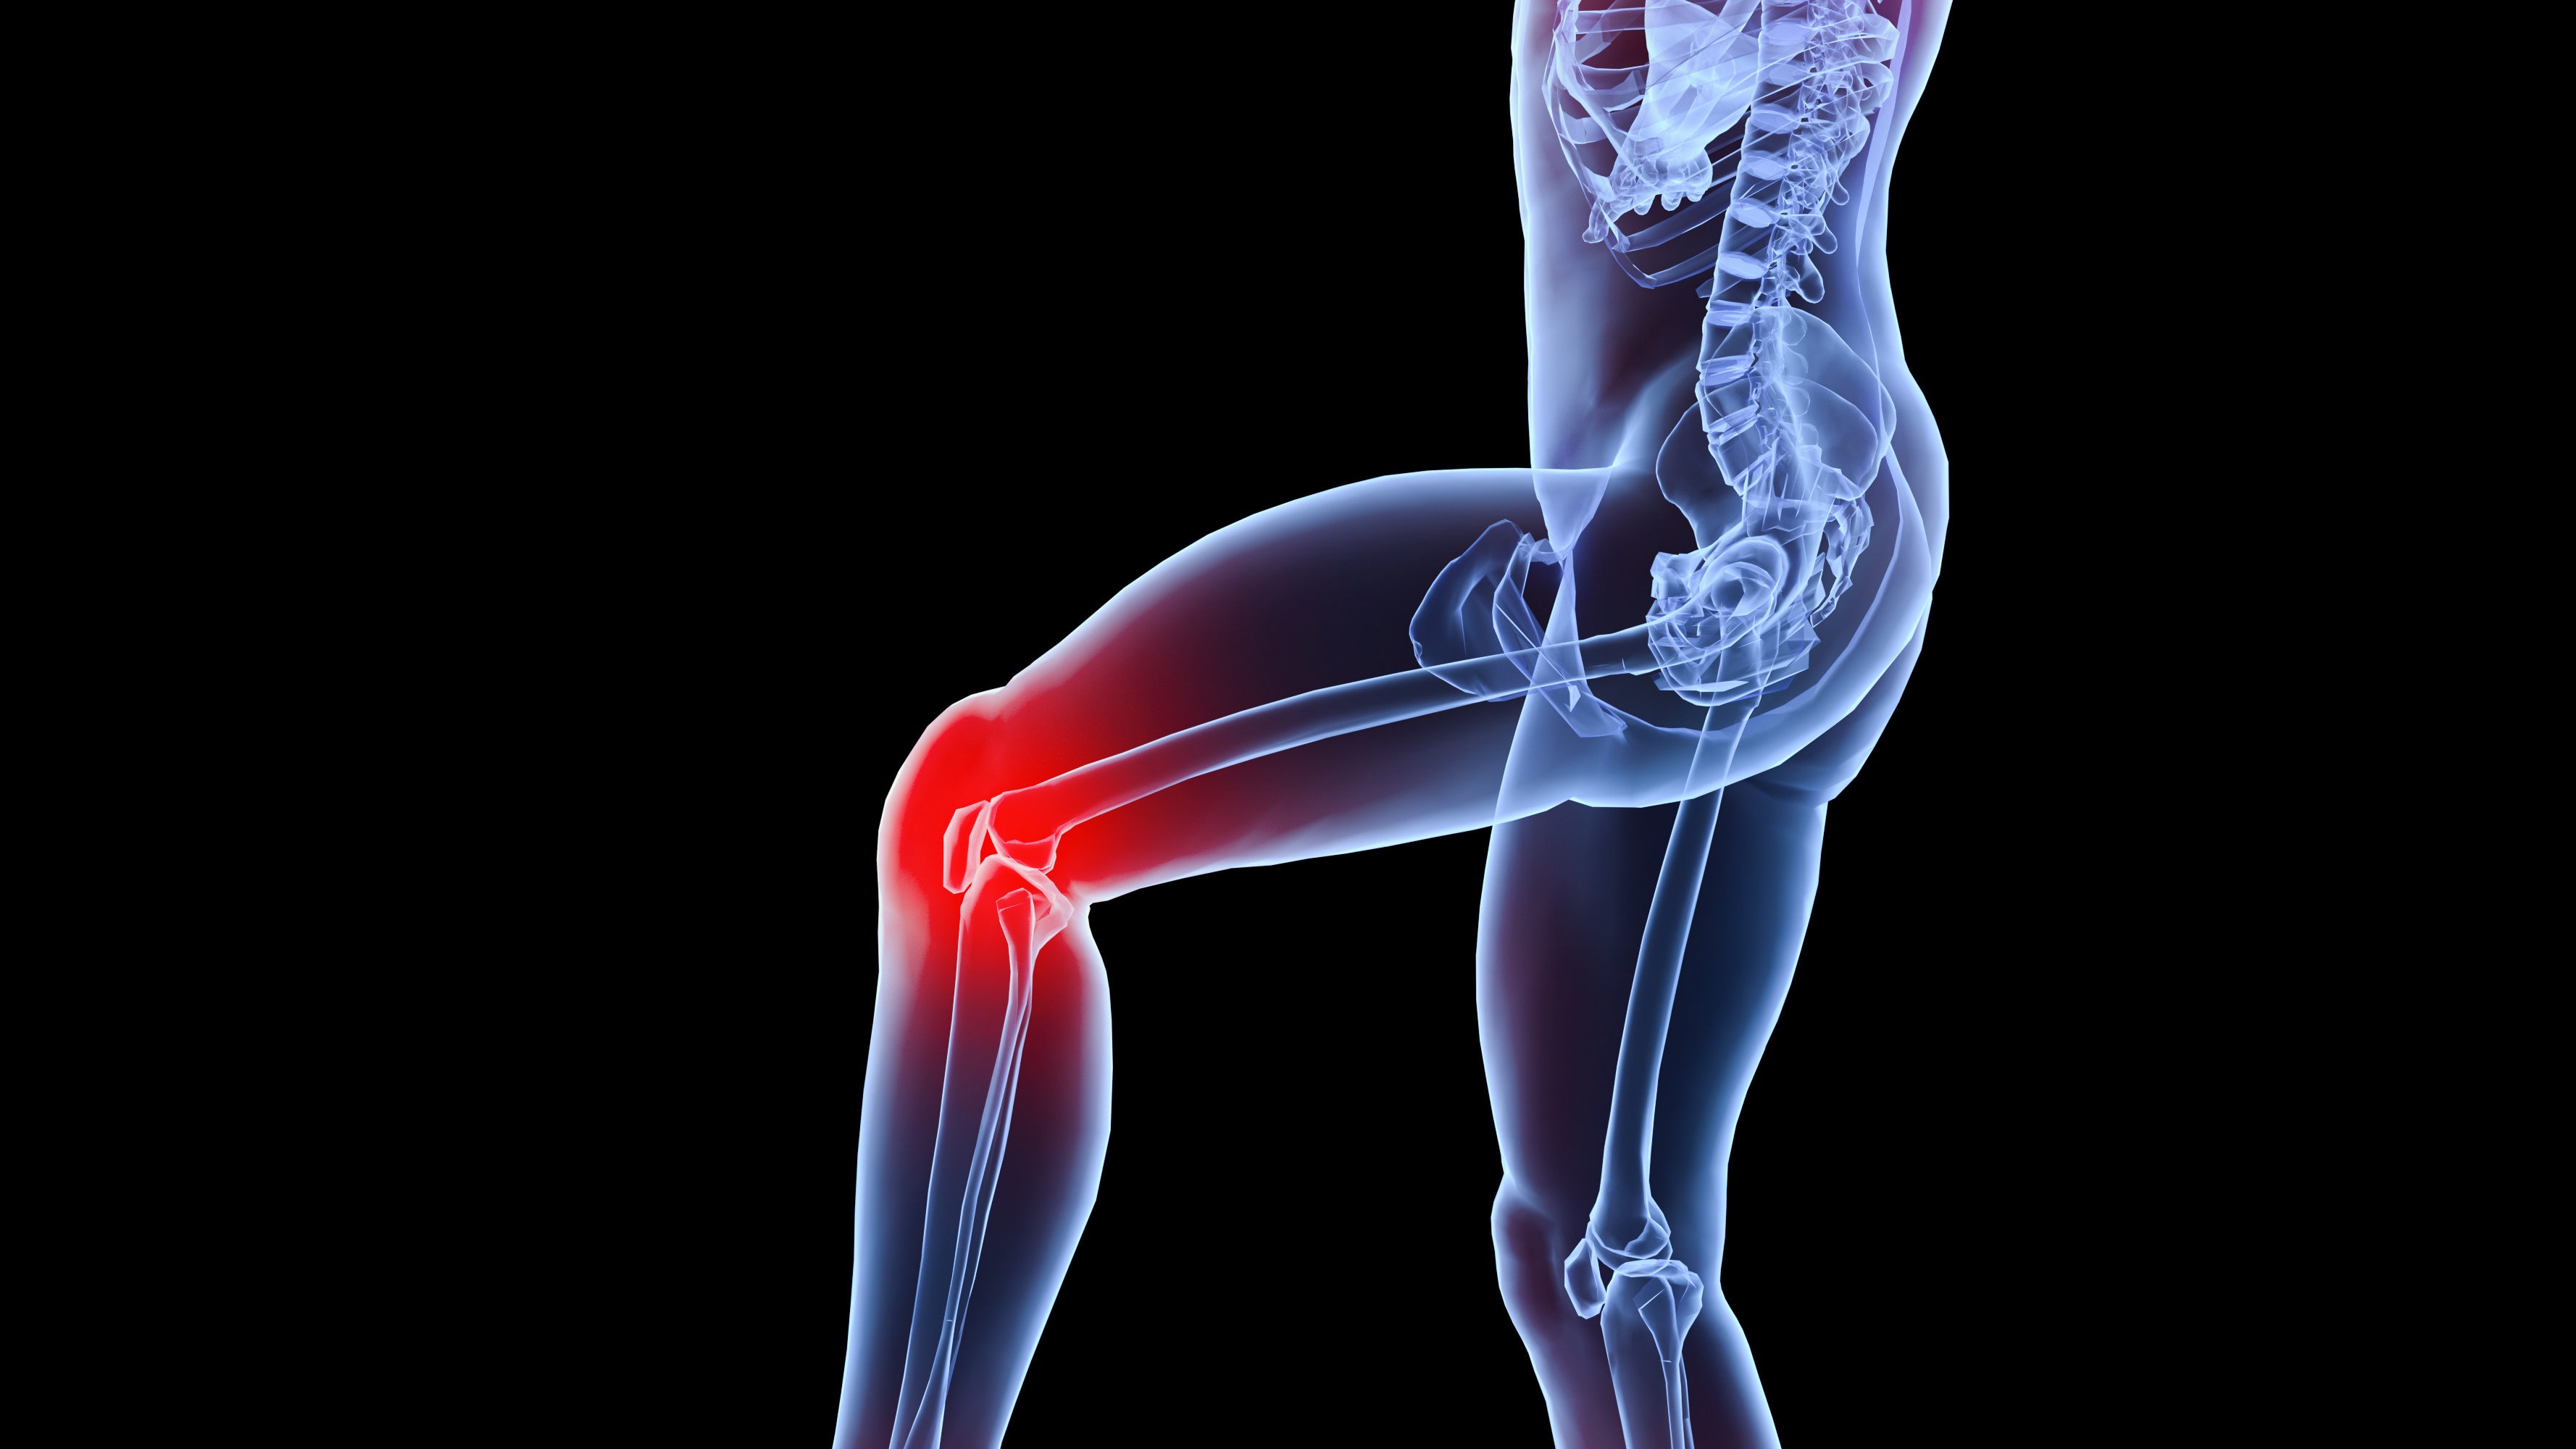

术后康复:膝关节屈曲90°活动受限的原因?

影响关节活动度的元凶之一